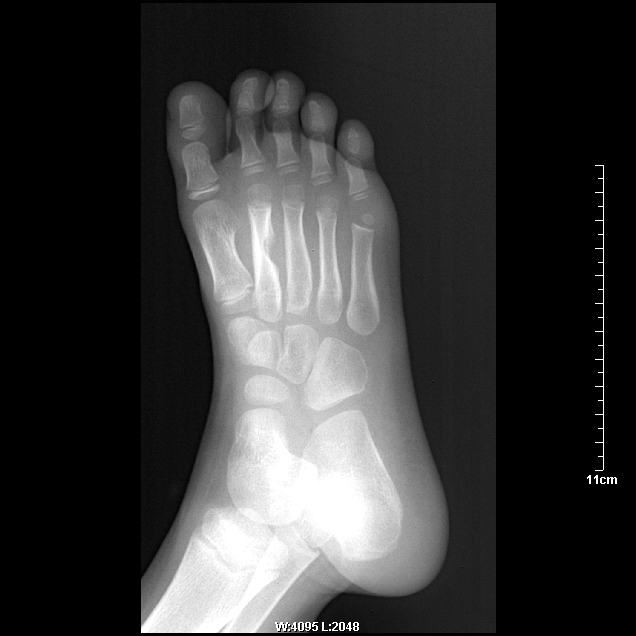

女 5岁  足底部(三、四跖骨处)针刺二月余,现局部红肿。

考虑 .第二跖骨慢性化脓性骨髓炎可能性大.

局部骨皮质增厚,密度增高。病史2月以上。应该首先考虑低毒性感染。同意大家意见。

考虑第二跖骨慢性化脓性骨髓炎可能性大。